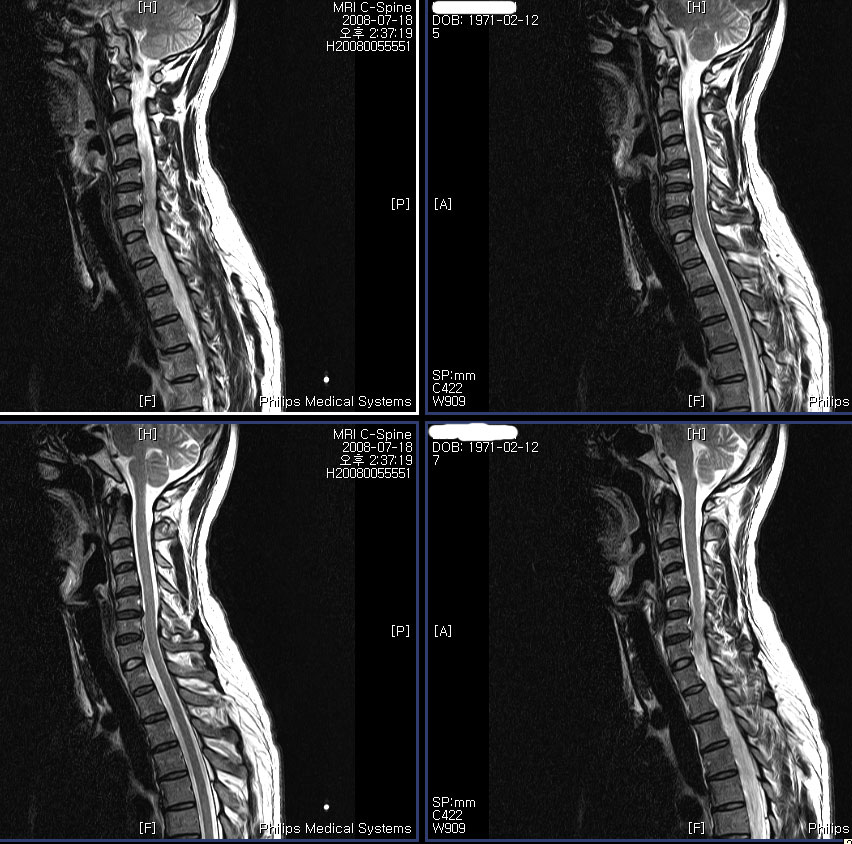

-------- mri ¿ ȣϽ Դϴ.------------- :,κ , Ʒκ(,ո) ٸ Ʒκ() ȭ- ȭ ǻ 콺 ۾ϱⰡ . 2008 5 Ȱ ٸ ȭ ִٰ 6뿣 ʿ Խϴ. MRIԿ 3 ġ Űֻ,ġ (ġ 1Ͽ1~2 ٰ ֱ ūǻ缱 ø ҽϴ) Űֻ縦 ̷ մϴ. ʹ ͳݰ˻ϴ ǥغ ˰ԵǾ Ϸմϴ. ̷ ڰ մϴ. ༺̶ ϼ̴µ ǻ缱Բ ģ ѻԴϴ. ڷ MRI纻 ֽϴ.Ϸ 帮ڽϴ. --------Ұ۳-------------- ũ, ֽϴ no 3366 date 2008-10-06 20:26:41 name ع (gaeul72@nate.com) IP: 220.83.43.174 3 ,ٸ , ϴ MRI Կ ༺ ũ Դϴ. ġ ġ ұϰ ٸ ȣ ͳ ˻ ϴ ǥغ ˰ Ǿϴ. ʹ ˾ƺ ᱹ ġ ϳ ߽ϴ. 12ð Ѿ ư ʹ ҽϴ. 켱 ù ϰ ҽϴ. ſ ũ پٰų ϴ° ߽ϴ. Ѱ ε 谳 ΰ Ѱ Ʊٴ ǰұ ߽ϴ. 3 ȣǴ Ȯ Խϴ. ġ ϸ鼭 迣 ߰ Ծ ߴµ ʾƵ ŭ ϴ. ġ ġᵵ ް ǥغ㼱Բ ˷ֽ ϰ е带 ٲ㰡 õ ߽ϴ. α ȿ ٵ ϰ ʹٰ մϴ. ϰ ʹ ٸ Ⱑ ϴ. ̾ µ ٵ ʹ ϰ ٰ ߽ϴ. Ƴ ϳ ϰ ʹٰ մϴ. ó Ͻô е鲲 õϰ ͽϴ. ---------Ұ ----------- http://3wboard.zicoree.com/New_Board/Board/Read.php?Page=1&dummy=1223309285&Board=compill-50-free1&No=3366&Search=&keyword=&period=10000 |